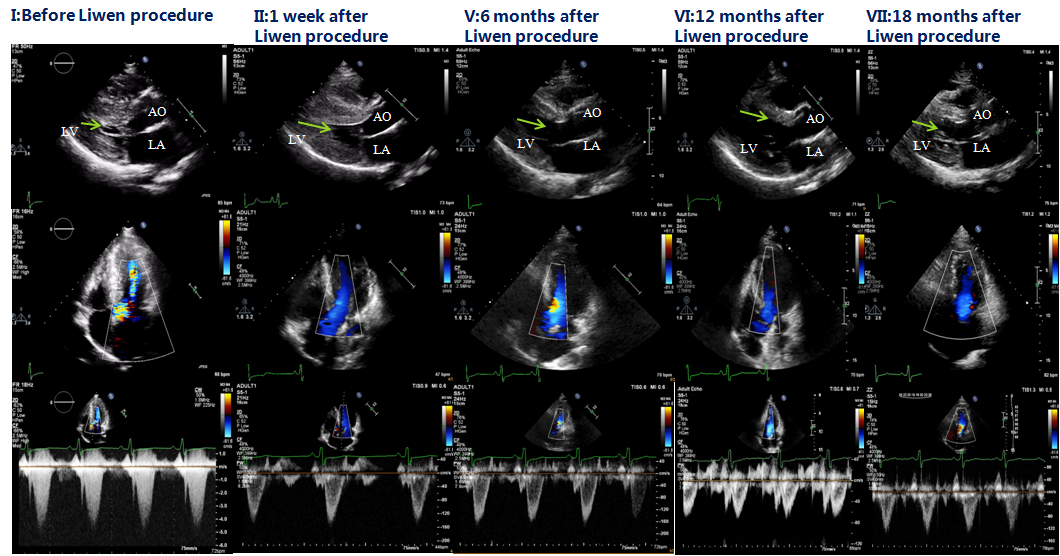

Liwen术式病例介绍

|作者:李静 刘丽文

|单位:空军(第四)军医大学西京医院